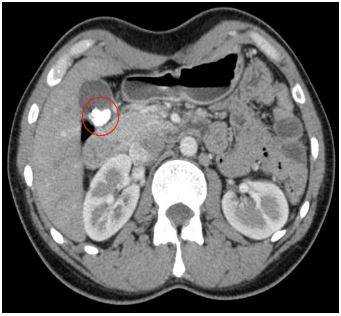

КТ (А) и МРТ(В) - картина холестериновой гранулемы

Эта дилемма волнует многих пациентов, но вид исследования выбирает лечащий врач, опираясь на результаты предыдущей диагностики и на конкретные жалобы. Отказываться от КТ уха из-за ложных соображений о вреде процедуры не стоит, современные мультидетекторные томографы позволяют минимизировать влияние лучевой нагрузки для большей категории лиц (исключение - беременные и дети, не достигшие 14 лет). В ряде наблюдений, особенно, если визуализируется опухолевый процесс, может понадобиться и МРТ, и КТ уха - эти способы взаимодополняют друг друга. Выполнение магнитно-резонансного сканирования обосновано, если после проведенной КТ остались сомнения в диагнозе. МРТ лучше демонстрирует менингоцеле, холестеатому, неврит лицевого нерва, внутричерепную патологию, вызванную процессами в среднем ухе, что не всегда показывает компьютерная томография высокого разрешения. КТ среднего уха часто не способна визуализировать степень возможной облитерации улитки после перенесенного воспаления или отдаленные последствия перелома височной кости. Точная оценка состояния имеет решающее значение для планирования кохлеарной имплантации.